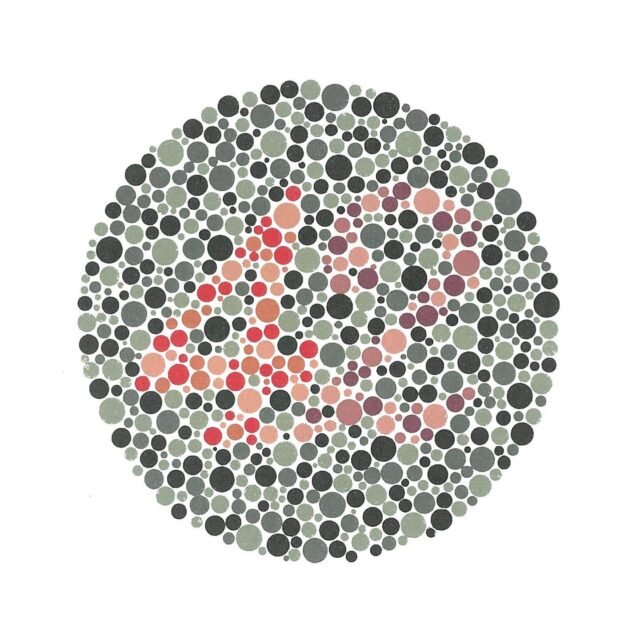

Daltonizam ili djelomična sljepoća na boje najčešće se može dijagnosticirati već u djetinjstvu. Postoje testovi kojima se utvrđuje percepcija boja i razlikovanje nijansi. Te testove čine grupe različito obojanih točkica koje formiraju neki oblik, provodi oftalmolog.